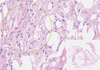

Fat Necrosis Flashcards

Fat Necrosis

Adipose Tissue

Collagen Fibers

Connective Tissue

Foamy Histocytes

Giant Multinuclear Macrophages

Granulocytes

Granuloma

Infiltrate with Granulocytic Prevalence

Lymphocytic and Plasma Cell Infiltrate